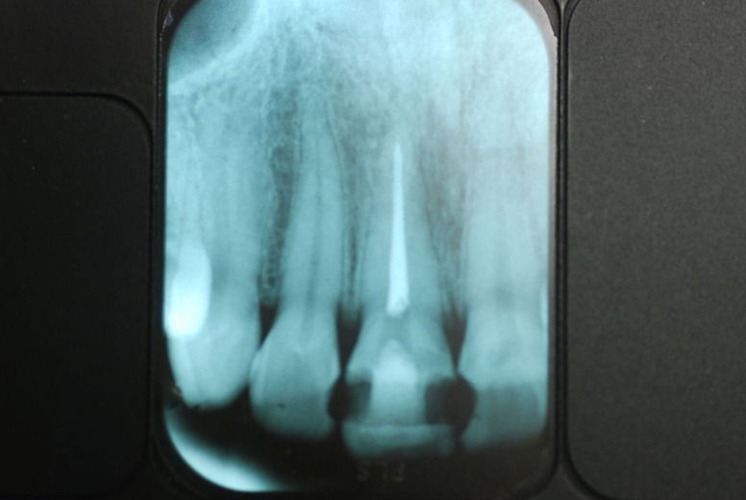

歯周病の疑いで東京のかなり遠方の方が来院されました。

驚くべきことですが、定期検診は受けていたそうです。しかしながら歯周病の指摘は受けたことがないそうです。

何故か?定期検診が虫歯のチェックのみになり、又肝心の歯周病の検査や歯周病の部分の予防や治療のためのブラシの使い方などを学んだ事がないのです。